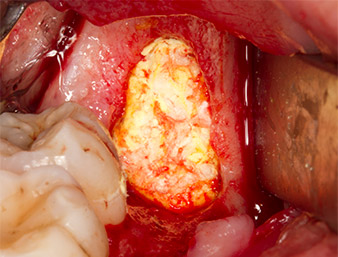

Fragments osseux

Fig. 13 : Les fragments osseux prélevés dans la zone d’intervention sont conservés dans un soluté physiologique isotonique stérile.

Puis le tissu osseux autogène (Fig. 13) est placé dans l’alvéole et le défaut osseux voisin (Fig. 14). Une membrane de collagène recouvre les fragments osseux à hauteur de l’os afin de protéger le nerf exposé (Fig. 15). Pour refermer le tissu mou ouvert, on utilise du fil de suture Vicryl, USP 4.0 (Fig. 16). Une préparation à base d’ibuprofène (Seractil 400 mg, 3x1) et un antibiotique associant amoxicilline et acide clavulanique (Augmentin 1 g, 2x1) sont prescrits en postopératoire.

Partie apicale de l'alvéole

Fig. 14 : La partie apicale de l’alvéole est recouverte du tissu autogène